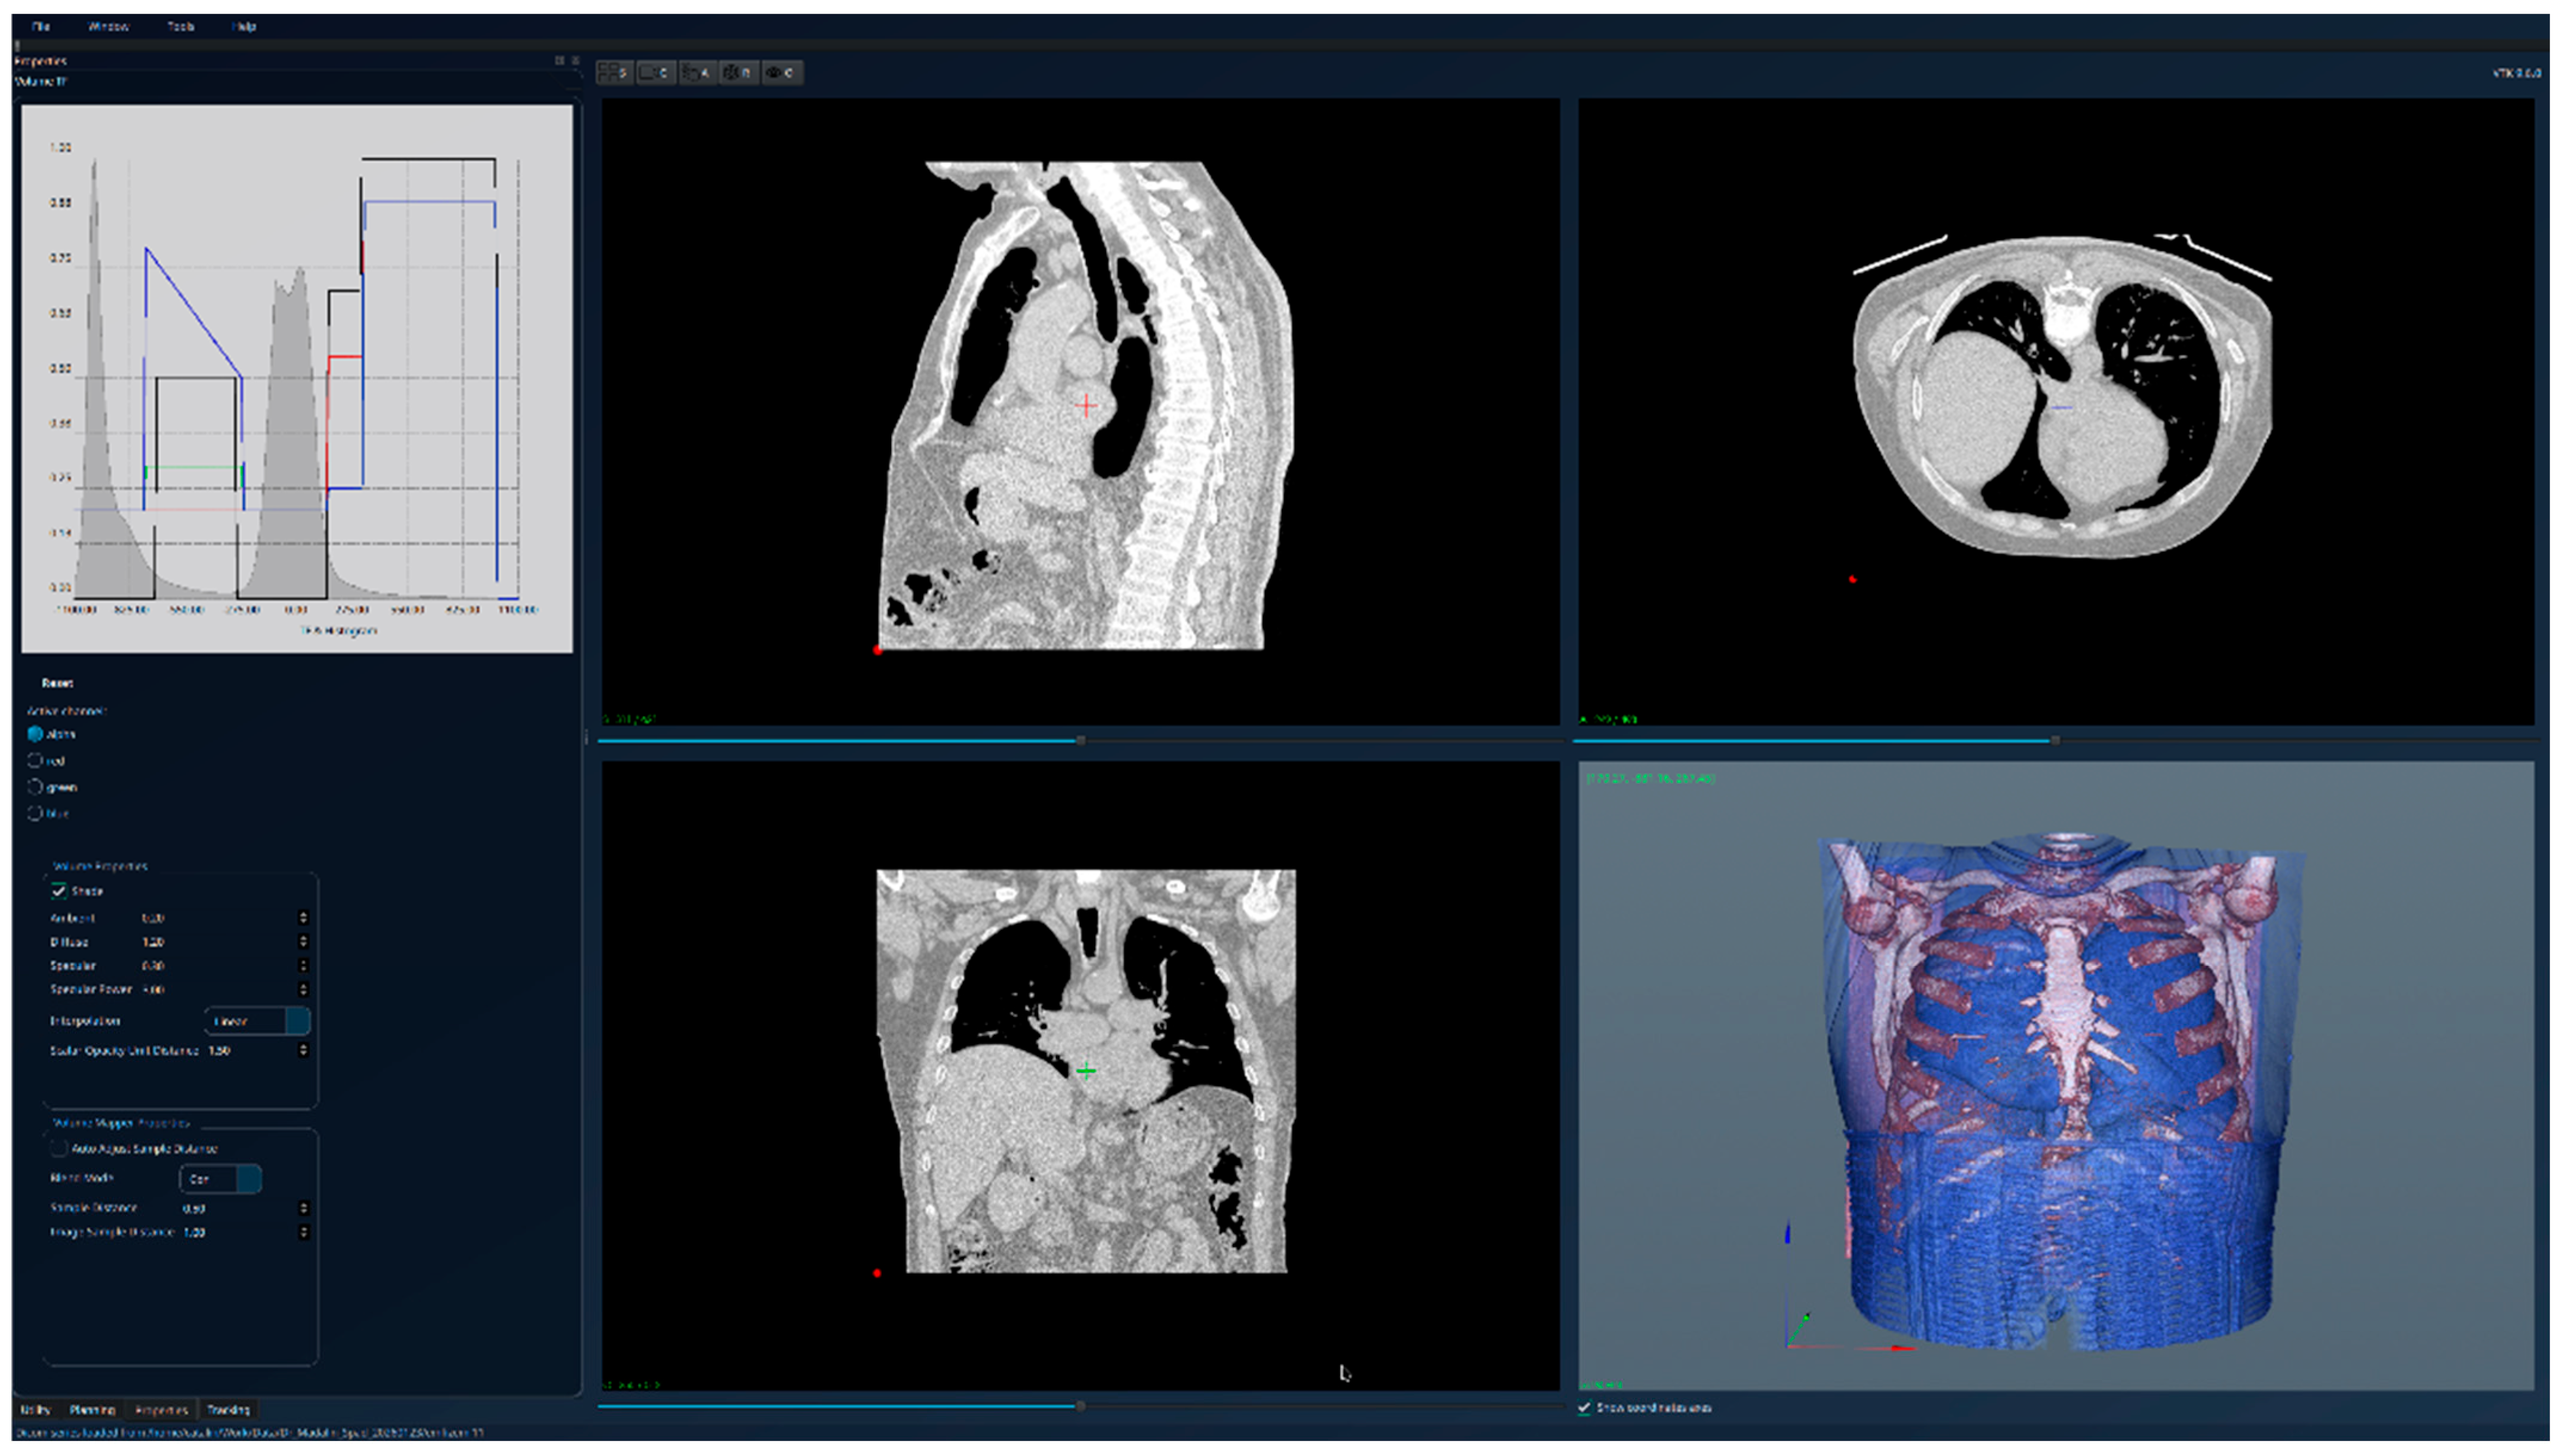

3. Results

| Patient 1 (healthy lungs) | 781 × 512 × 373 | 0.5 × 0.5 × 1 | 58,696 |

| Patient 1 (healthy lungs) | Br60 | 1.5 | Siemens Healthineers | SOMATOM go.Top |